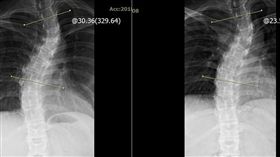

背痛照X光 她脊椎歪如「飛龍衝天」

某早餐店一名35歲莊姓女店員,每次只要出力揉麵糰、烤...

2018/11/08 15:00